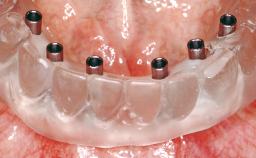

Conventional Loading of Eight Implants in the Maxilla and Final Restoration with a Full-Arch Gold-Ceramic FDP

Loading Protocol Conventional or early

Interim Prosthesis during Healing Removable Removable